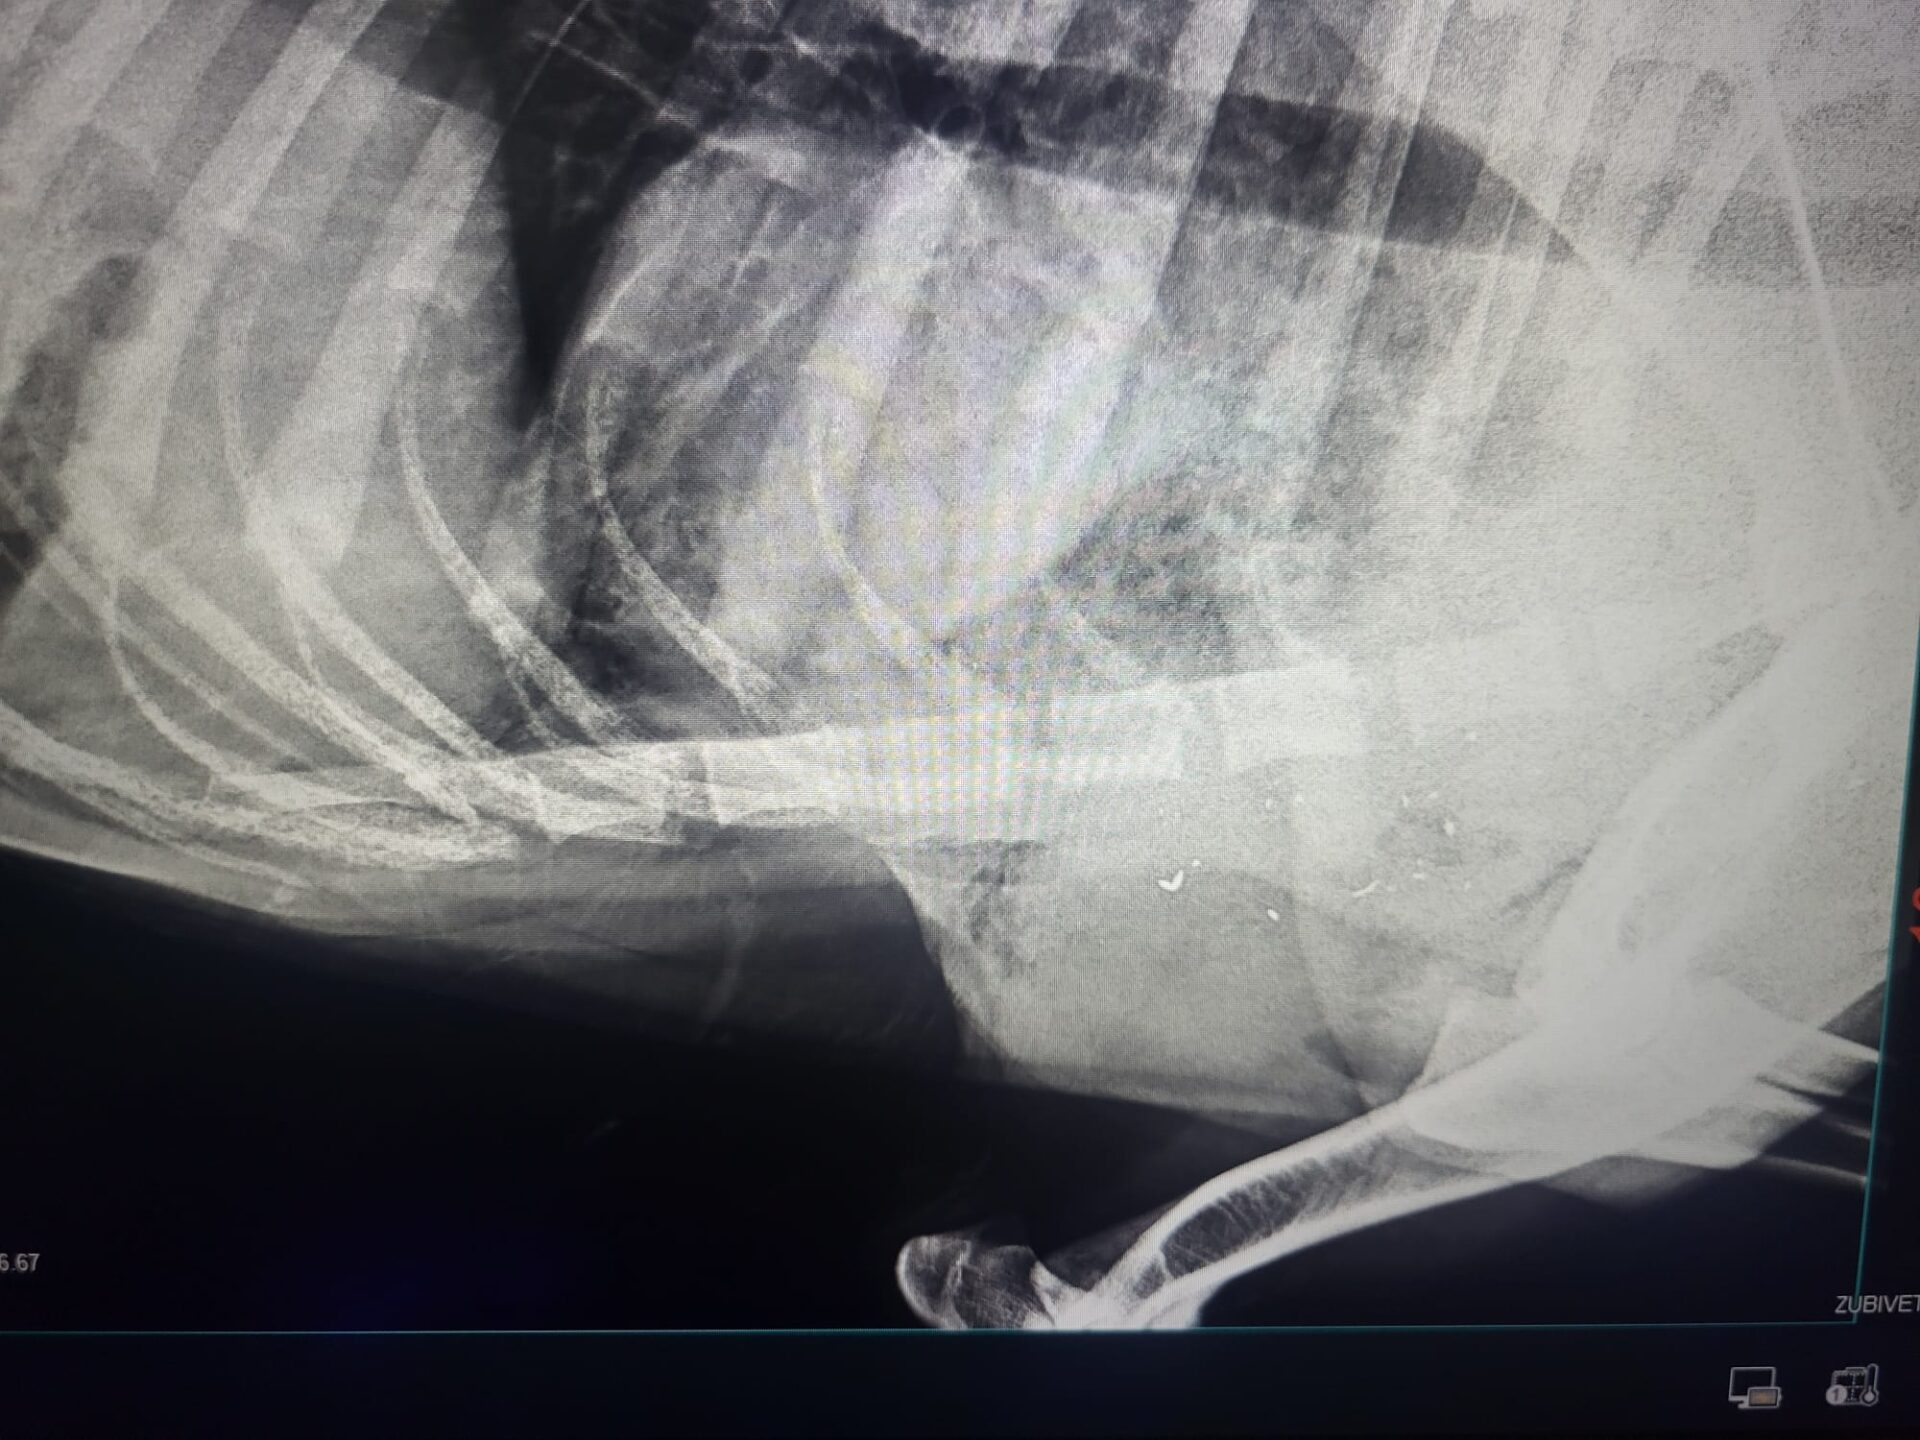

Am dus apoi câinele la medicul veterinar, dar rănile erau prea grave și a murit, pentru că din ce mi s-a spus sunt gloanțe care se fragmentează în momentul în care intră în animal”, a relatat Vasile Petrar.